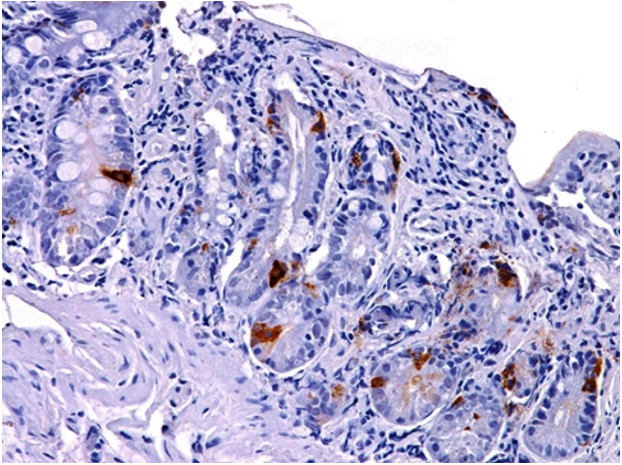

Хронический активный субатрофический дуоденит при целиакии. Экспрессия CD 8. ИГХ, увел. 100 |